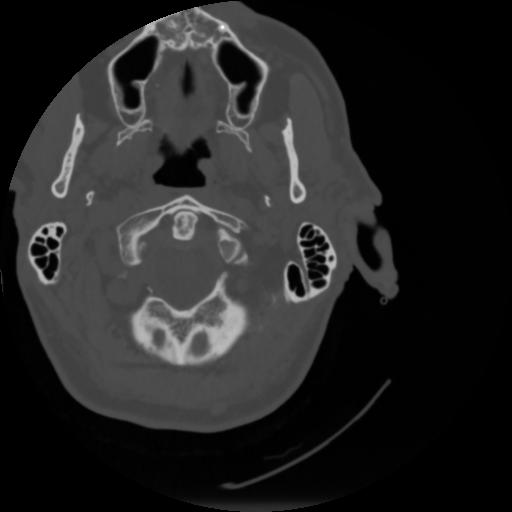

4 CEREBRO,,Vol,0.5,CEREBRO,,